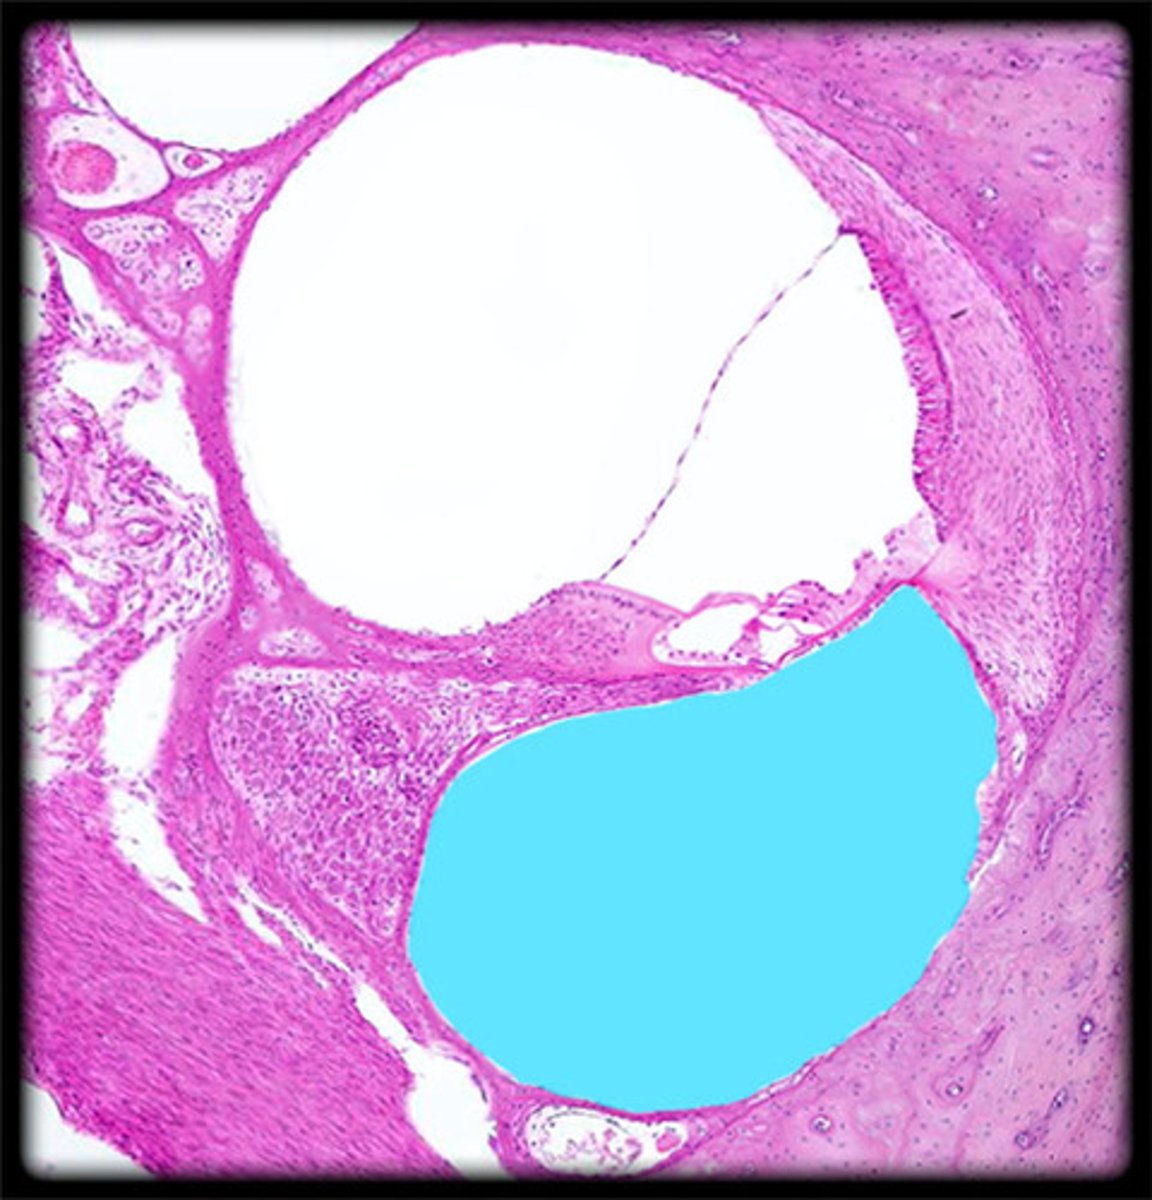

anterior chamber

posterior chamber

choroid

ciliary body

iris

lens